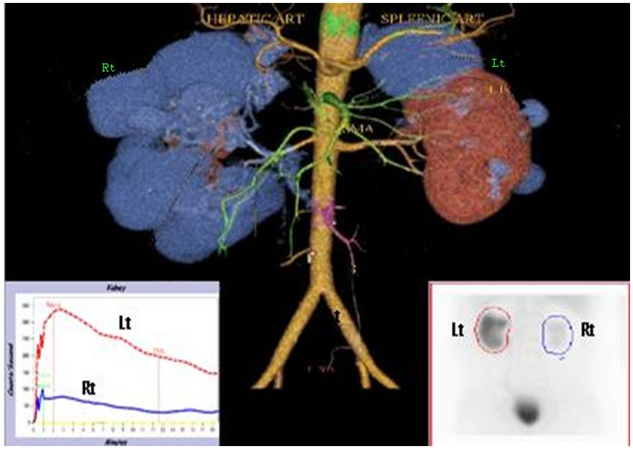

Prostate malignancy was ruled out. Plasma CEA and CA19-9 were normal, stool occult blood negative, upper GI endoscopy showed gastric ulcer with duodenal erosions with biopsy from lesions ruling out malignancy, colonoscopy showed multiple colonic diverticula (Figure 3).

Figure 3 Coloscopy showing colonic diverticuli(arrow).